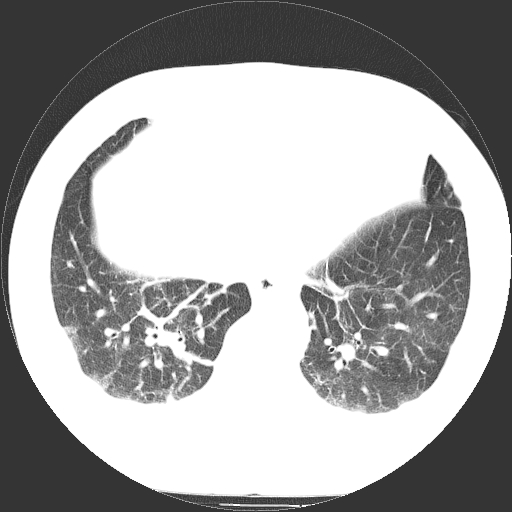

标题: CT21804:男,65岁,咳嗽、咳痰、发热5天。 [打印本页]

男,65岁,咳嗽、咳痰、发热5天。

慢支 肺间质纤维化合并感染!

支气管扩张合并感染,胸膜肥厚

考虑慢支并感染,肺间质纤维化。

两肺间质性炎症并感染

两肺间质纤维化,支扩合并感染,双侧胸腔积液

支持慢性支气管、肺间质纤维化合并感染。

慢性支气管炎并感染,支扩,双侧少量胸腔积液.